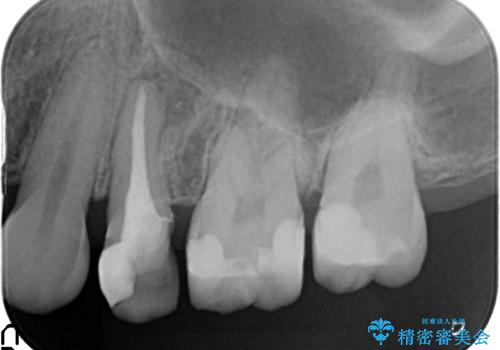

- 他院にて左上5番目の歯の根管治療を行っていたが、痛みが引かないため当院にいらっしゃった方の症例です。

左上5は再根管治療を行い症状の緩解を確認後、オールセラミッククラウンによる補綴を行いました。

左上6、7番目の歯もしみるとのことだったので古い樹脂及び虫歯を除去後、オールセラミッククラウンによる補綴を行いました。

※右上5は歯肉縁下まで虫歯だったため歯冠長延長術を提案しましたが希望されませんでした。